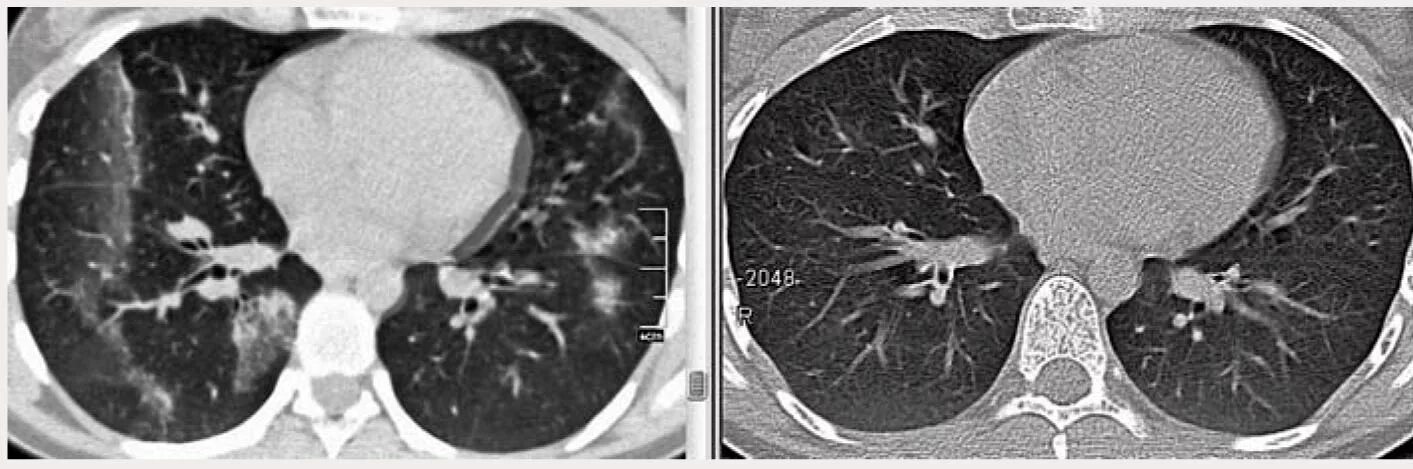

Уплотнения паренхимы по типу